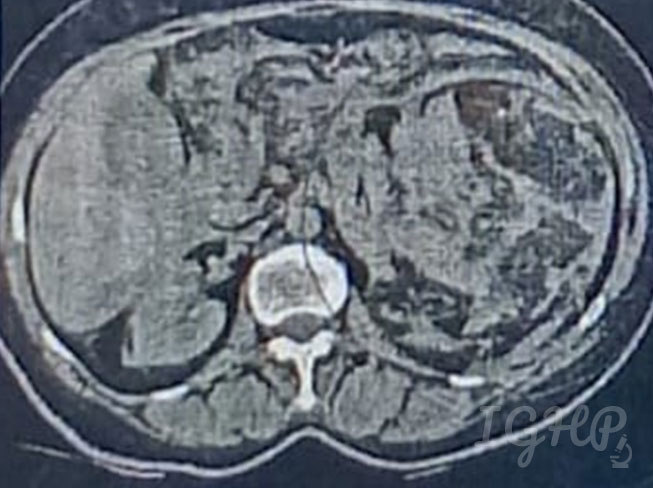

64-year-old male history of road traffic accident presented to emergency department with severe pain abdomen. Plain CT showed ruptured mass in upper pole of kidney. From the images below identify the likely disease.

Radiology-

Plain CT-Large heterogenous exophytic space occupying mass lesion noted arising from upper pole of kidney measuring 11.4 x 10 showing fat attenuation with multiple irregular haemorrhage.